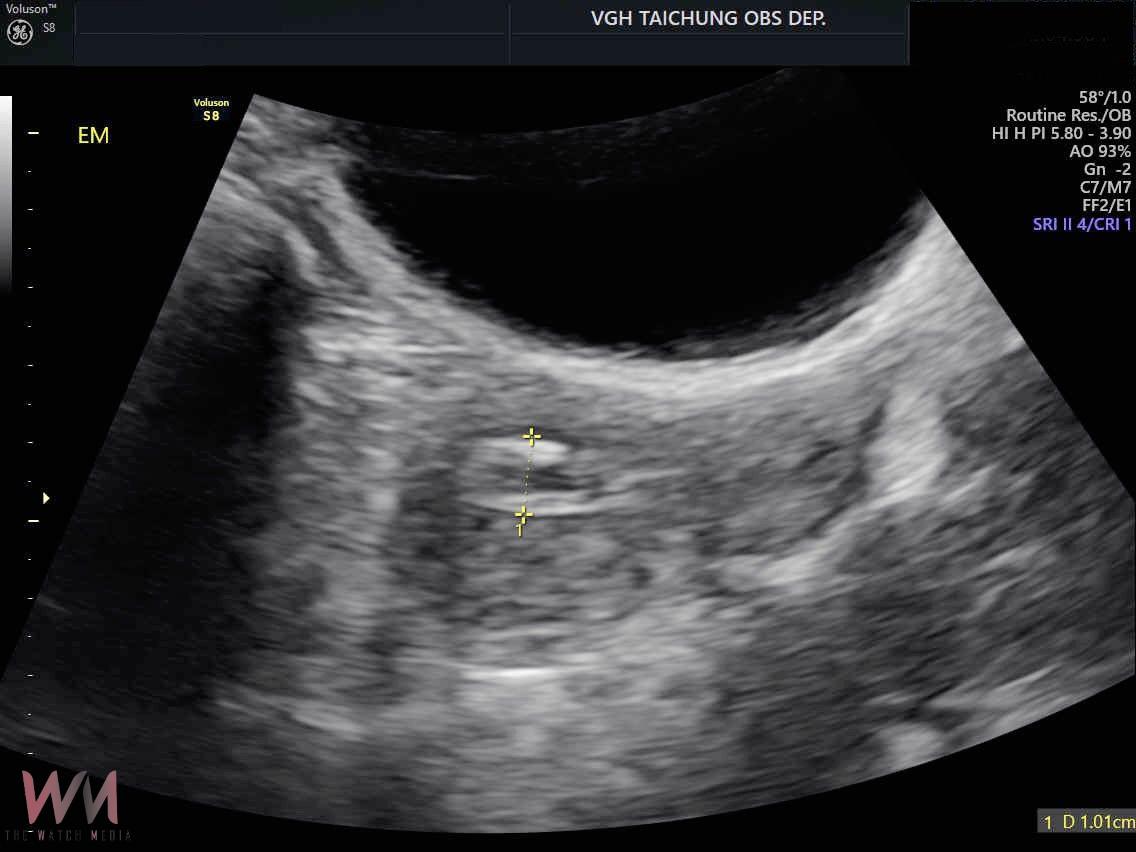

起初李小姐至診所,超音波檢查發現子宮內膜增厚,先服藥物治療,但出血未改善,轉診至臺中榮總,切片診斷為子宮內膜癌,須手術切除子宮、卵巢及骨盆淋巴腺治療。

孫珞也提醒婦女們,造成停經後出血原因包括:陰道及子宮頸萎縮、息肉或肌瘤等良性原因;子宮內膜亦可能發生異常增生,雖然尚未達到惡性程度但仍需積極手術處理;惡性原因則以子宮內膜癌最為常見,其他還包括子宮頸癌、卵巢癌、陰道或外陰癌。

如果民眾屬子宮內膜癌的高風險群,包括初經早或停經晚、長期月經不規則、肥胖、糖尿病、代謝症候群、曾具多囊卵巢症候群病史、不曾懷孕、使用荷爾蒙治療等狀況,建議應定期接受婦科檢查。停經後子宮內膜癌的患者有90%都會出現陰道出血的症狀,更年期後若有不正常出血,不論出血天數或血量,一定要盡快就醫檢查,才不會錯過治療時機。